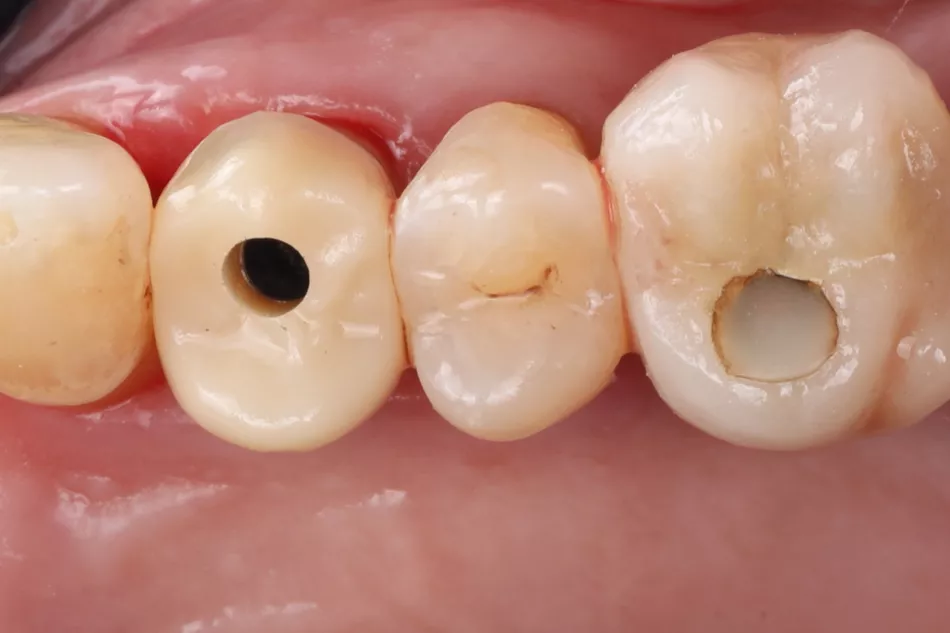

Phase IV: After a 2-month osseointegration period, delayed loading was initiated. A digital impression was captured directly on the Healfit® SH healing abutment acting as a scanbody, minimizing abutment disconnections and reconnections thus preserving peri-implant tissue integrity (Fig 5 a-d & 6).

The implant site was scanned (Straumann SIRIOS™ X3), and STL files were used to design a single crown on an X-Base® Ti-base (OPFLEX526). A long-term provisional crown was 3D-printed in resin, cemented extraorally, and delivered with adjusted occlusion for 6 months to monitor tissue stability and function (Fig 7-9) .

5a. 5b. 5c. 5d. Intraoral scan captured with Healfit® SH acting as a scannable healing screw.